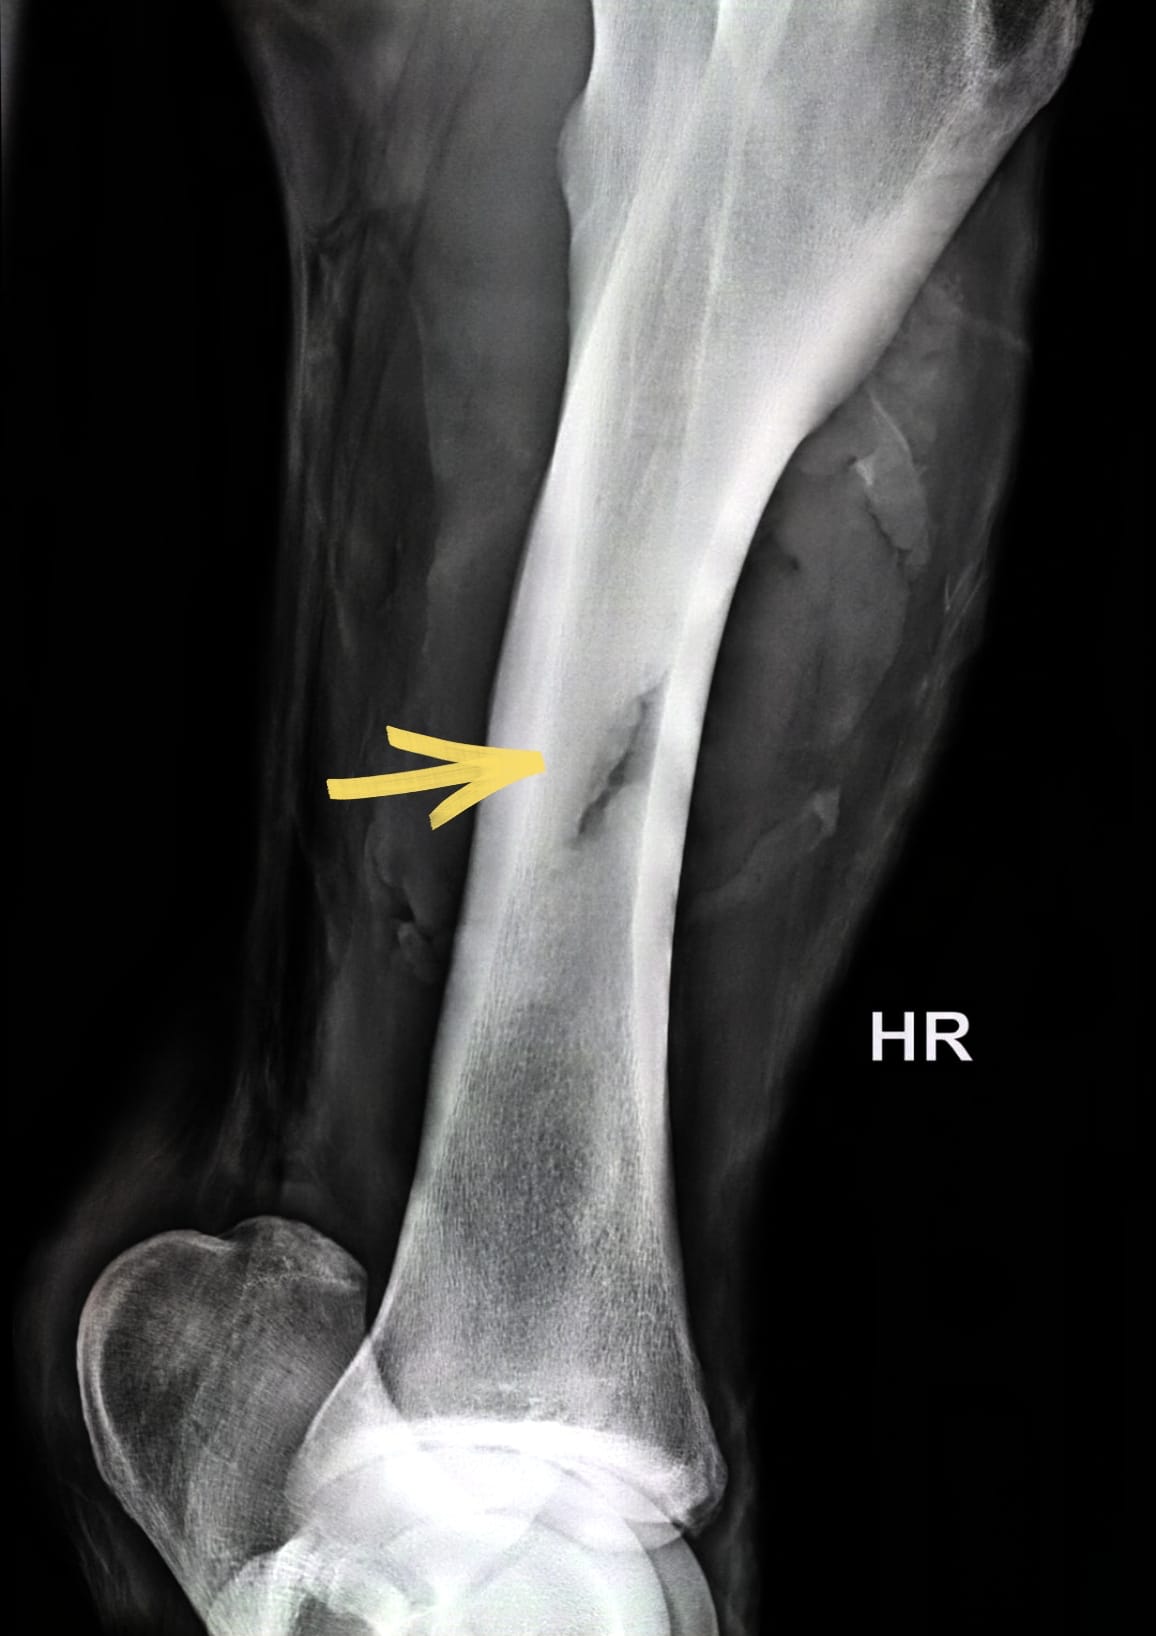

Allein die Befreiung des panischen Pferdes aus seiner misslichen Lage erforderte viel Einfühlungsvermögen. Was uns dann aber erwartete, stellte uns doch vor eine schwierig zu lösende Aufgabe: Neben der stark blutenden Wunde mit großem Hautverlust erbrachte die röntgenologische Untersuchung, dass der Knochen des Unterschenkels auf einer größeren Länge auch noch angebrochen war.

Was ein Dilemma! Eigentlich hätte die schwer zugängliche, deutlich kontaminierte Wunde in Vollnarkose versorgt werden müssen, der Schockzustand von „Hans“ und der angebrochene Knochen schlossen dies aber strikt aus, da die große Gefahr bestand, dass der Knochen beim Aufstehen nach der Narkose vollständig brechen könnte.

Aufgrund des angebrochenen Unterschenkelknochens wurde das Bein mit einem dicken Polsterverband unter Einbeziehung von stabilisierenden Gipsbinden so gut wie möglich geschient. Die erste Zeit verbrachte „Hans“ natürlich auf unserer Intensivstation, damit wir ihn 24 h überwachen und medizinisch versorgen konnten. Er kämpfte wie ein Löwe und allen Befürchtungen zum Trotz verheilte die Wunde zwar langsam, aber ohne gefährliche Wundinfektion und der angebrochene Knochen wuchs wieder glatt zusammen. Was ein Glück!